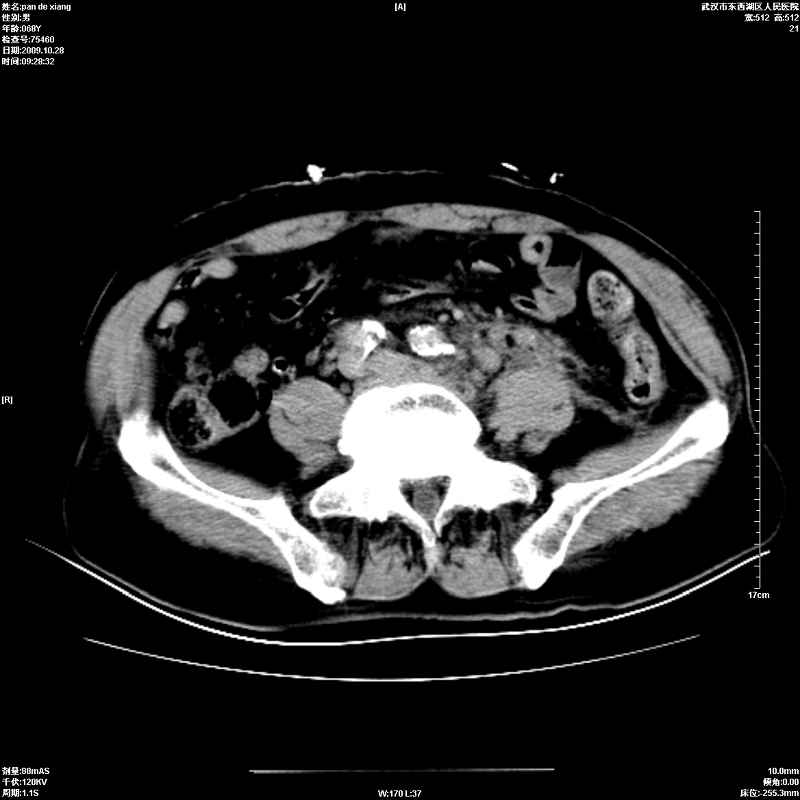

以下是引用杀毒软件在2009-10-28 20:41:00的发言:[br]结合临床考虑---白血病双肾改变或淋巴瘤。

以下是引用zxl51642在2009-10-29 9:59:00的发言:[br]结合临床“单克隆免疫球蛋白血症”,考虑双肾为继发损害并肾功能不全(尿中大量igg及少量iga、igm等大分子免疫球蛋白滤出所致继发损害),椎前软组织肿块为髓外造血。与浆细胞瘤有区别,平扫时有战友说的很清楚。